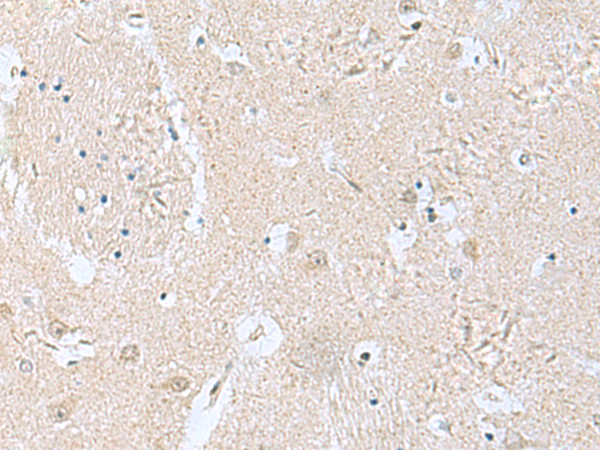

IHC positive control: |

Human brain |

IHC Recommend dilution: |

100-200 |